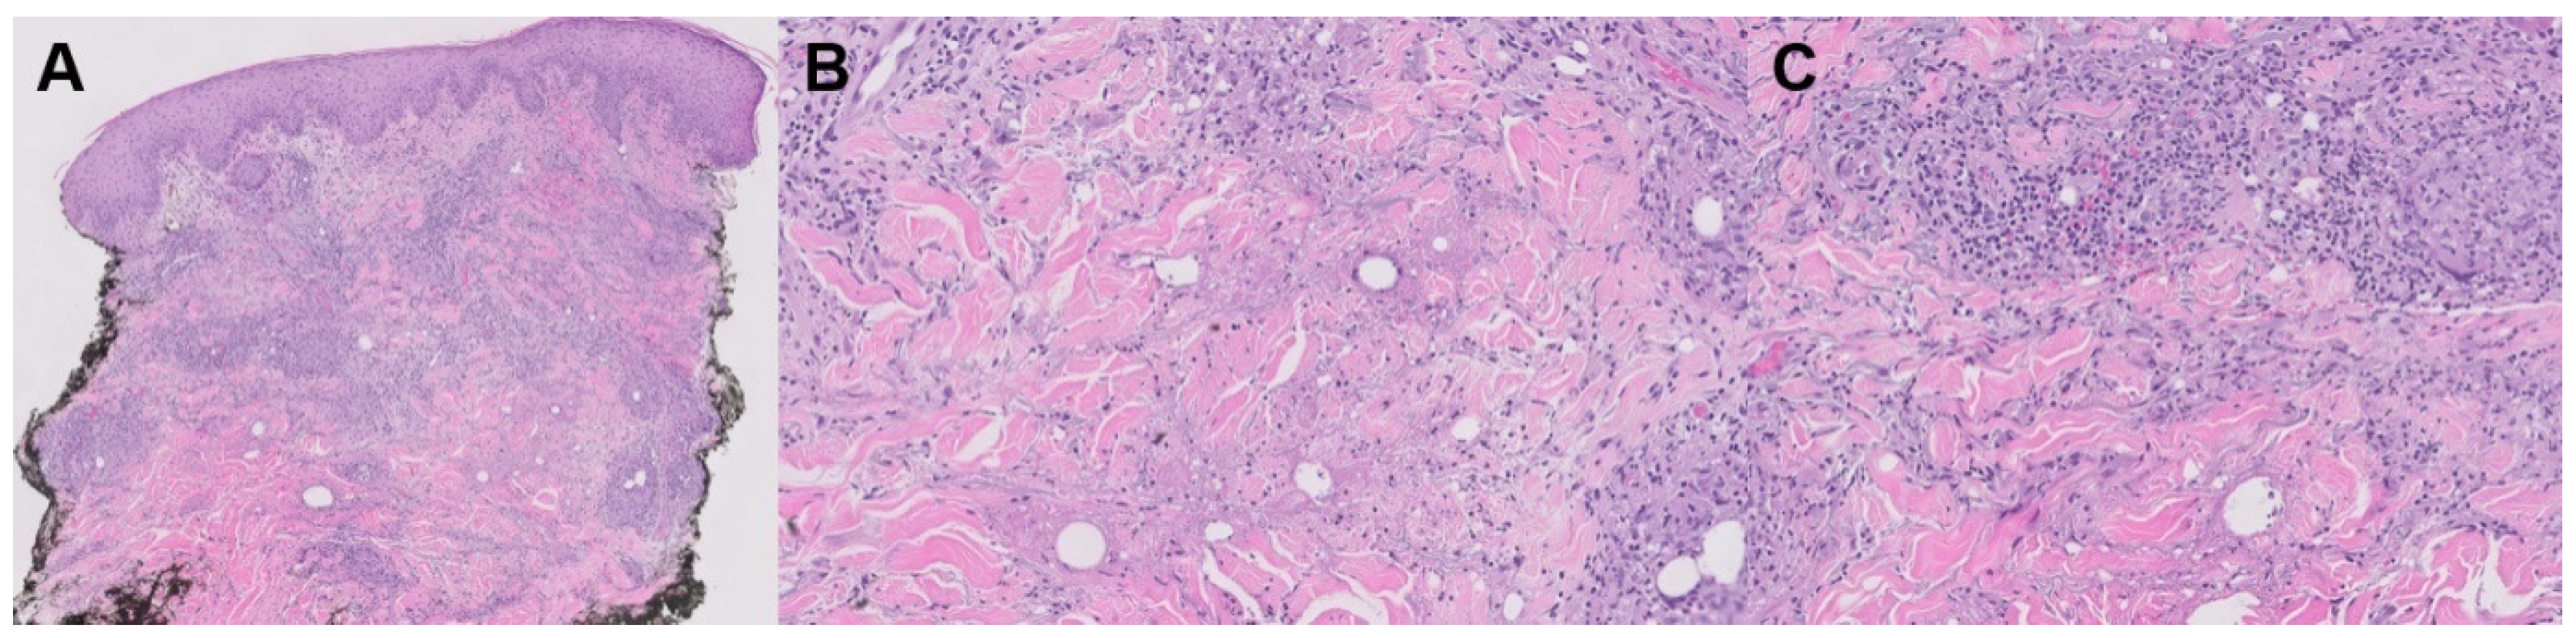

3.1.1. Rheumatoid Nodules

| Rheumatoid nodules | -Positive RF -Smoking | -Palisading macrophages -Granulation tissue | -Hands, fingers, elbows, feet | -SSZ, TCZ, RIX, colchicine, DPA -Corticosteroid injections -Surgery |

| Accelerated rheumatoid nodulosis | -MTX use -HLA-DRB1*0401 | -Palisading macrophages -Granulation tissue | -Hand, feet, ear | -Stop triggering drug -HCQ, DPA, SSZ, colchicine |

| Rheumatoid nodulosis | -No erosive arthritis -Negative RF | -Palisading macrophages -Granulation tissue | -Pretibial areas, feet, scalp, malleoli | -Prednisone, NSAIDs -Topical TAC, HCQ, DPA, PN -Surgery |